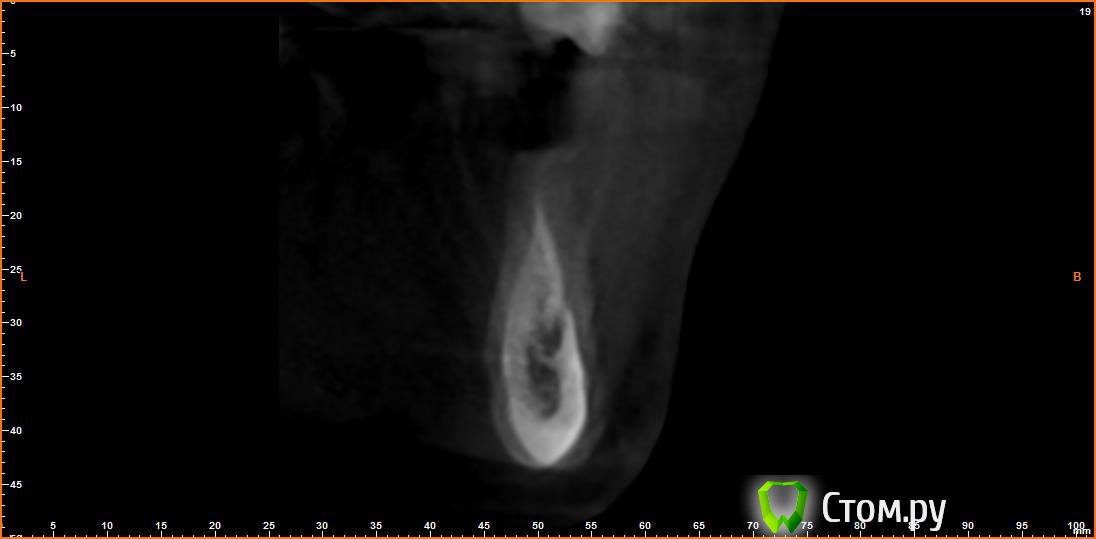

Opimar Опубликовано 21 июня, 2014 Автор Поделиться Опубликовано 21 июня, 2014 Выкладываю еще. Пошагово от 34-37 Ссылка на комментарий

Bier Опубликовано 21 июня, 2014 Поделиться Опубликовано 21 июня, 2014 Выкладываю еще. Пошагово от 34-37темная точка достаточно высоко, это по моему не нерв, нерв ниже, я правильно понимаю? Ссылка на комментарий

Opimar Опубликовано 21 июня, 2014 Автор Поделиться Опубликовано 21 июня, 2014 темная точка достаточно высоко, это по моему не нерв, нерв ниже, я правильно понимаю?Да он ниже и язычнее. Провел от менталиса там еще запас есть. Ссылка на комментарий